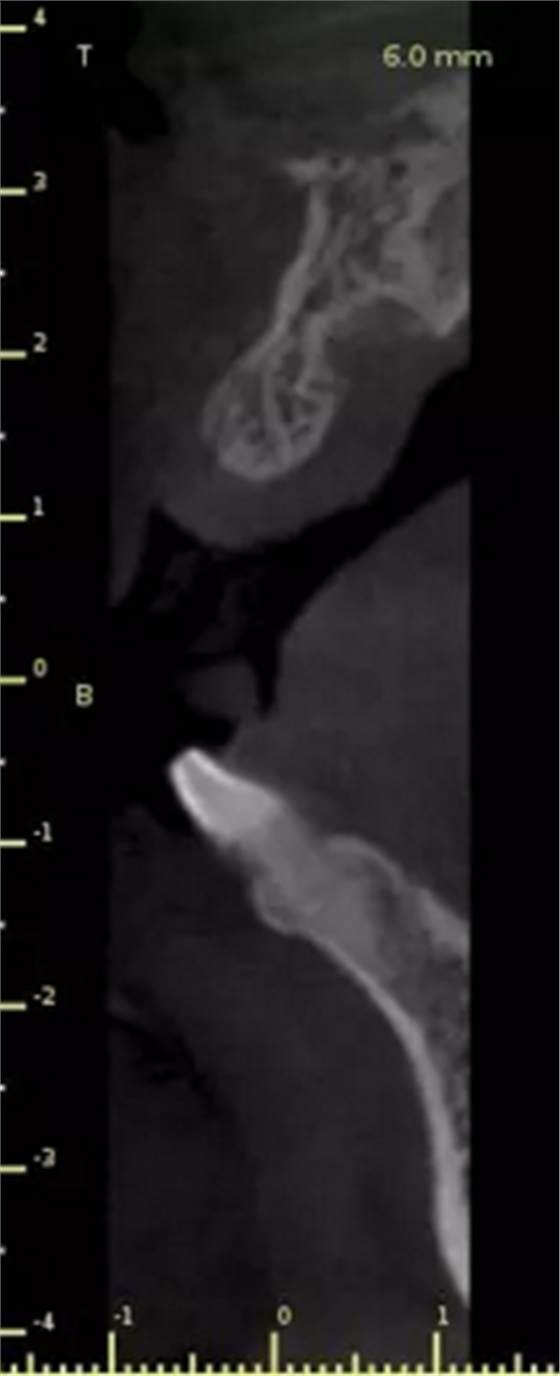

1.術(shù)前CT

2.術(shù)前植體設(shè)計(jì)